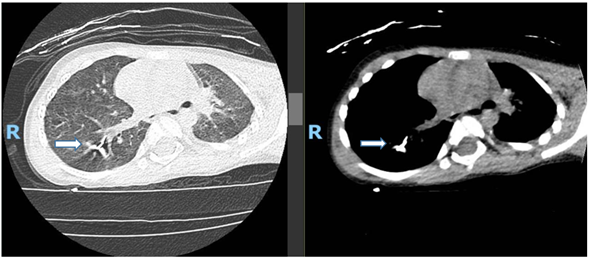

A 6-year-old boy with a known history of cerebral palsy and spastic quadriplegia presented to the emergency department (ED) two hours after inhaling a metallic dental bur during a dental procedure at an outpatient clinic. His initial physical examination was unremarkable. A chest X-ray performed in the ED revealed the FB in the right lower lung zone. A subsequent CT scan confirmed the presence of a 2.5 cm metallic FB lodged within the bronchioles of the right lower lung.

Figure 1: X-ray showed foreign body in right lung lower zone.

Figure 2a: CT scan chest (horizontal view) showed: Metallic foreign body at the bronchioles of the right lower zone measured 2.5cm.

Figure 2b: Coronal view.